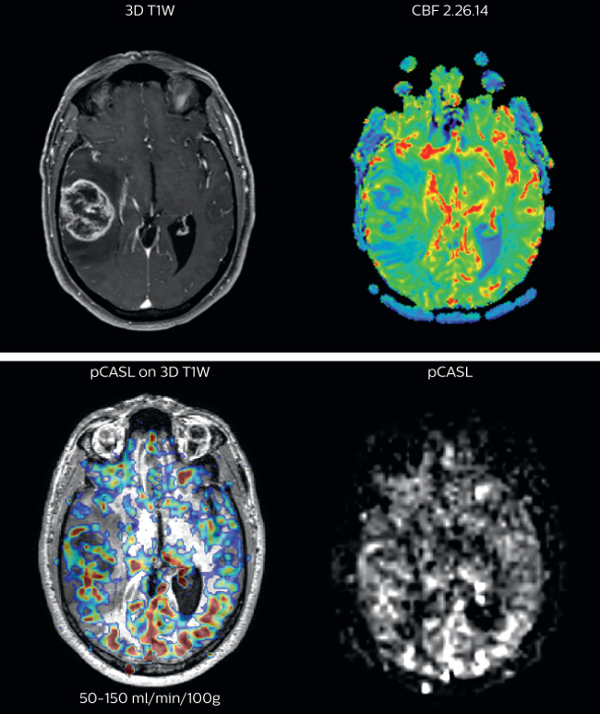

The pCASL perfusion map overlaid on the 3D T1 image demonstrates a peripheral rim of elevated cerebral blood flow corresponding to the centrally necrotic glioblastoma. The pCASL-generated CBF closely approximates the rim of elevated rCBV obtained with DSC contrast-enhanced perfusion imaging. Scanned on Achieva 3.0T dStream